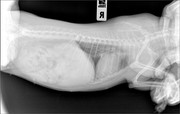

Коллапс трахеи форум